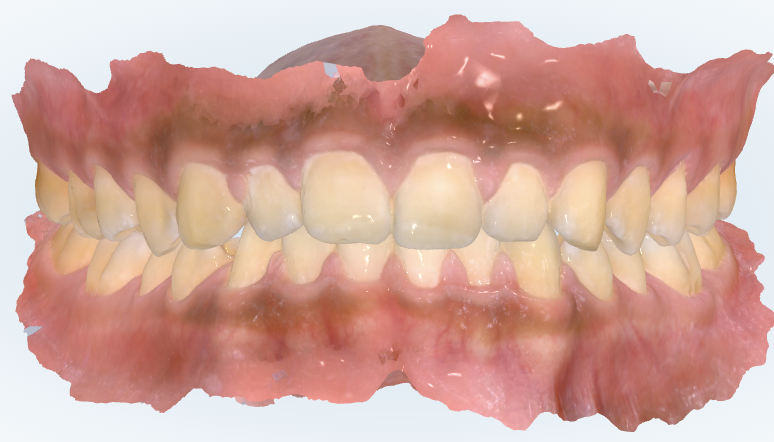

初診時の画像診断

ある程度歯並びは整っていますが、軽度のガタガタと噛み合わせが不十分なところが残っています。

今の噛み合わせを見ると、全体的に奥歯も噛めていて生活に支障はないと思います。しかし、当たっていない、浮いているところが残っているのが分かります。

上下の歯が最後まで噛み合い切っていない状態です。

犬歯である前から3番目の歯や、その後ろの前から4番目と5番目の歯に段差やねじれが残っているので、当時そこが気になっていた可能性はありますね。

治療の途中で止まった感じは確かにあります。